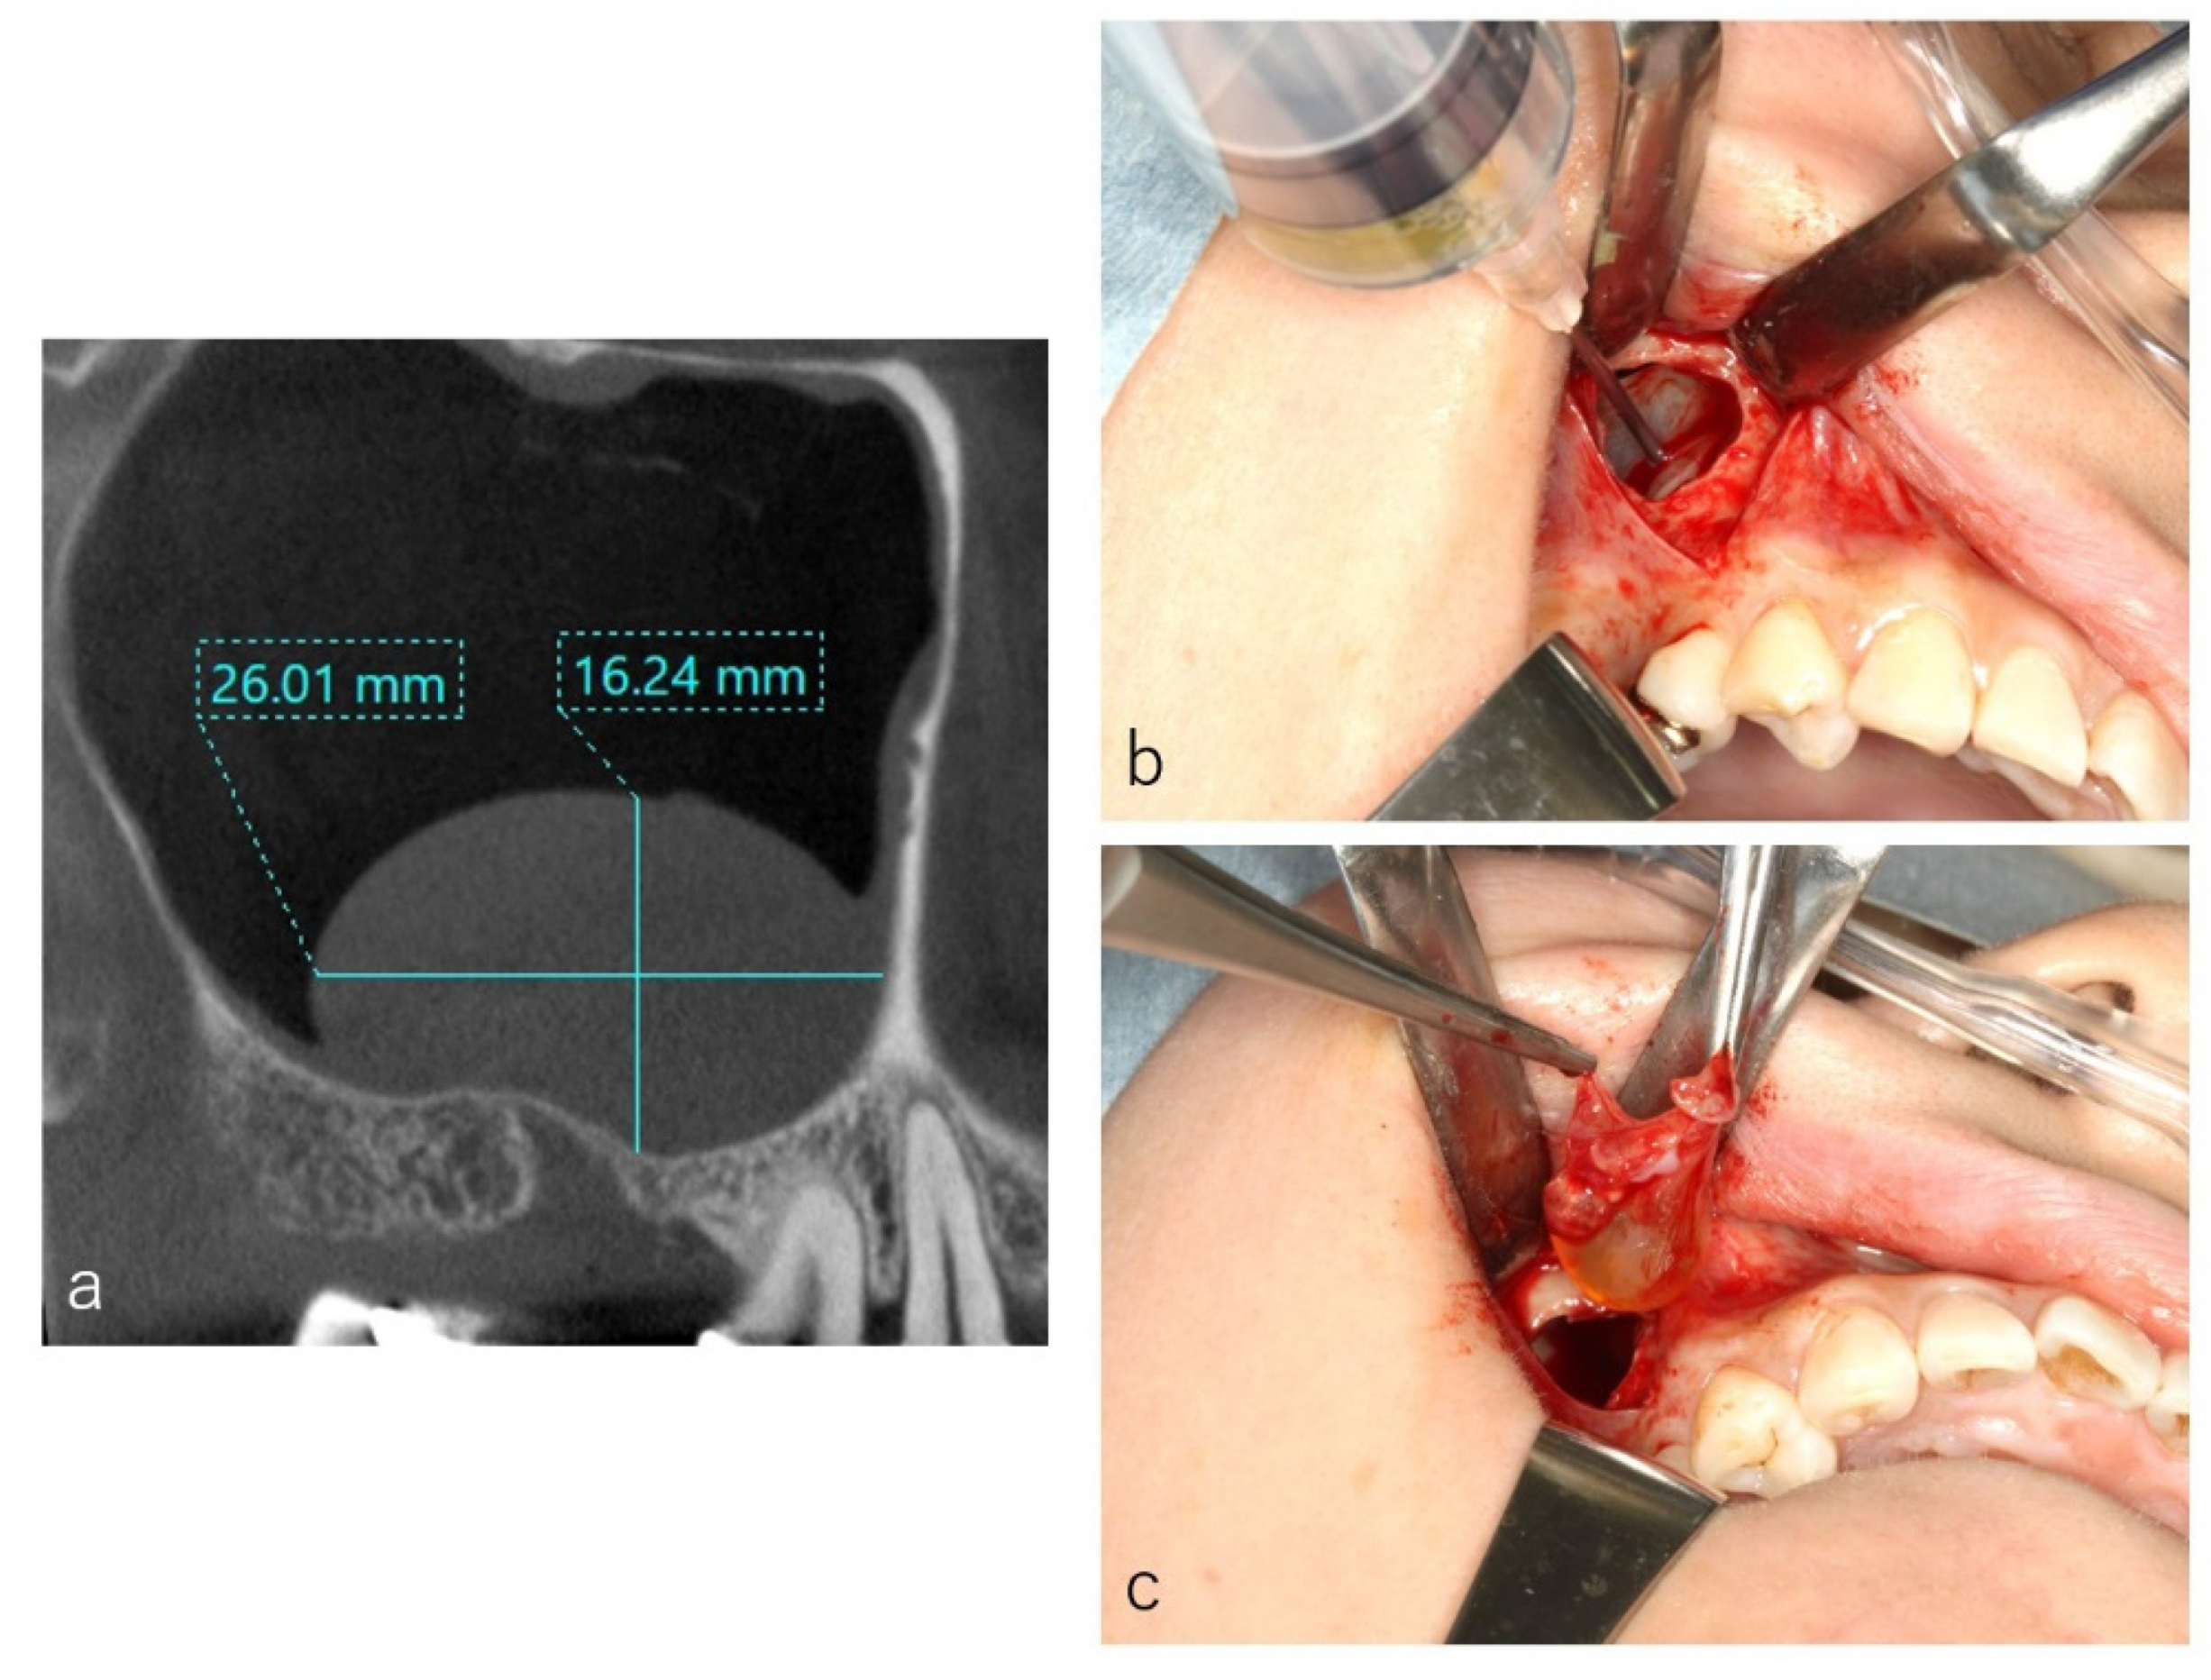

2.2. CBCT Evaluation

2.3. Surgical Procedure

3.1. Histology of the Frontal Wall

3.2. CBCT Evaluation of the Cystic Lesions

3.3. Types of Colors and Contents of the Cystic Lesions

3.5. Surgery and Clinical Progress